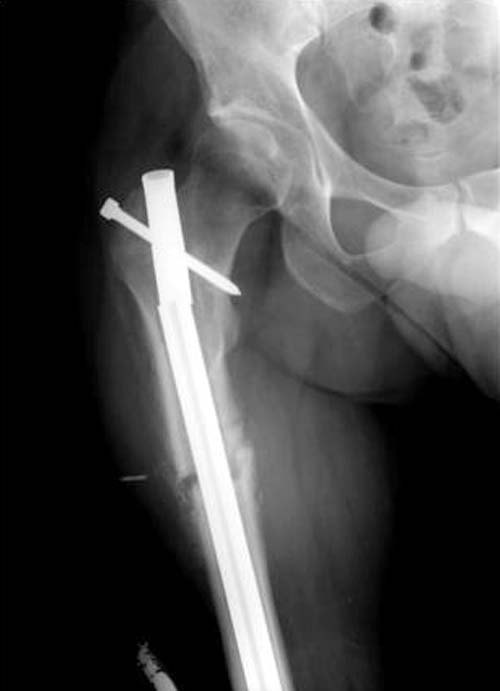

Имя     : 4 Fem nonunion postop lat.jpg

Тип     : image/jpg

Размер  : 24230 байтов

Описание: отсутствует

Url     : http://weborto.net:8080/pipermail/ortho/attachments/20111214/0c6bb1fc/attachment-0007.jpg

Тактика замены на более толстый гвоздь вроде правильная, и возможно у Вас получится с первого раза. Но без специальных трюков гвоздь удержать трудно, потому что между точкой на верхушке трохантера и старым каналом в пириформис почти отсутствует стенка. Без стенки трудно удержать гвоздь латерально и без блокирующих приспособлении гвоздь найдет старый канал. Конечность поведет и винт в головке срежется. Без опыта проведении блокирующих спиц, о которых  говорит Александр, вся затея окажется фиаско! Отклоняющие в передне-заднем направлении спицы в проксимальном отделе бедра немного страшновато, с повреждением седалищного нерва!

Для решения проблемных состояний некоторые коллеги выбирают только малоинвазивные методы, забывая другие методы лечения. Желание восстановить малоинвазивно это хорошо, но если имеется возможность полного восстановления  открытым методом - надо использовать. Вылеченный ложный сустав лучше, чем повторение процедур по поводу несостоятельности Гамма гвоздя...

Поэтому хотел предложить альтернативную технику, открыть место ложного сустава субвастус доступом и кортикотомия, одномоментное удлинение, аппозиция латерального кортекса. Для фиксации Blade Plate с коротким клинком при возможности или обычная прямая преконтурированная 4.5 мм пластина с медиальным костным графтом.

По-моему, такая простая техника решит проблему склерозированного старого ложного сустава намного дешевле, чем гвоздь, и без необходимости обьязательного ЭОПпри установке Гамма.

Надеюсь, мои опасения окажутся чрезмерными, и Вы покажете правильно установленную Гамму, и успешный результат лечения.